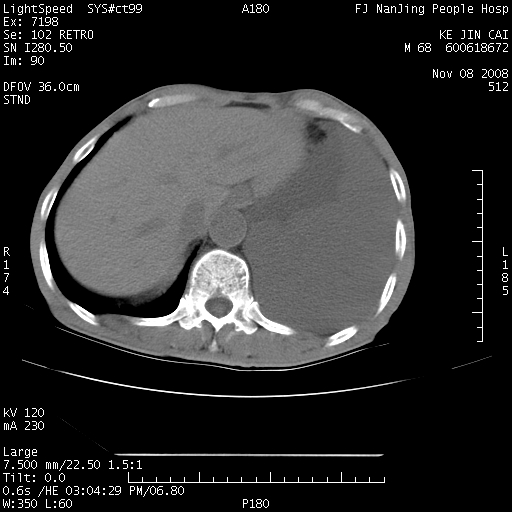

是个很有看头的病例,咋人气那么不旺?没多少人兴趣呢?这个病例几大怪:1   恶性肿瘤侵犯心肌左房怪,心肌一般不会被恶性肿瘤侵犯吧?2   左下肺均匀实变怪,内无含气,有别一般不张实变,含气肺泡完全为液体取代,而非一般不张实变的肺萎陷,冷不丁还以为是肿大的脾脏3   肿瘤本身怪,像tb肺不张4   这么有看头的病例没人气怪。呵呵。

左肺恶性肿瘤侵犯肺动脉,左心房内瘤栓,胸膜转移。

左肺恶性肿瘤侵犯肺动脉,左心房内瘤栓,胸膜转移,少见,学习了。